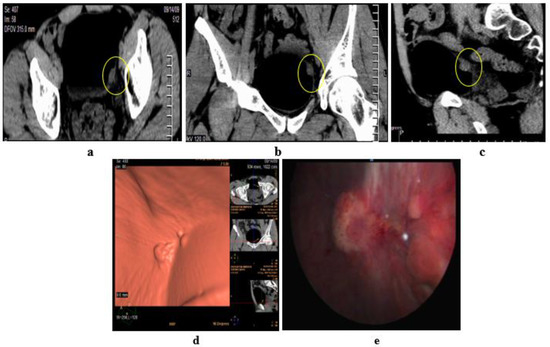

2.4. CT Urography

2.5. Virtual Cystoscopy (VC)

- Noncontrast CT of the pelvis subsequent to air/CO2 filling via a urethral catheter, then virtual reconstruction of images.

- Delayed phase of MDCT urography, then CT virtual cystoscopy reconstruction.

- Arslan, H.; Ceylan, K.; Harman, M.; Yilmaz, Y.; Temizoz, O.; Can, S. Virtual computed tomography cystoscopy in bladder pathologies. Int. Braz. J. Urol. 2006, 32, 147–154, discussion 154. [Google Scholar] [CrossRef] [PubMed]

- Kivrak, A.S.; Kiresi, D.; Emlik, D.; Odev, K.; Kilinc, M. Comparison of CT virtual cystoscopy of the contrast material-filled bladder with conventional cystoscopy in the diagnosis of bladder tumours. Clin. Radiol. 2009, 64, 30–37. [Google Scholar] [CrossRef]

- Vining, D.J.; Zagoria, R.J.; Liu, K.; Stelts, D. CT cystoscopy: An innovation in bladder imaging. AJR Am. J. Roentgenol. 1996, 166, 409–410. [Google Scholar] [CrossRef] [PubMed]

- Teama, A.H.; Darweesh, A.E.-m.N.; Abol-Enin, H.A.; Abouelkheir, R.T. Role of multidetector computed tomography virtual cystoscopy in evaluation of urinary bladder carcinoma. Egypt. J. Radiol. Nucl. Med. 2014, 45, 543–554. [Google Scholar] [CrossRef][Green Version]

- Nambirajan, T.; Sohaib, S.A.; Muller-Pollard, C.; Reznek, R.; Chinegwundoh, F.I. Virtual cystoscopy from computed tomography: A pilot study. BJU Int. 2004, 94, 828–831. [Google Scholar] [CrossRef]